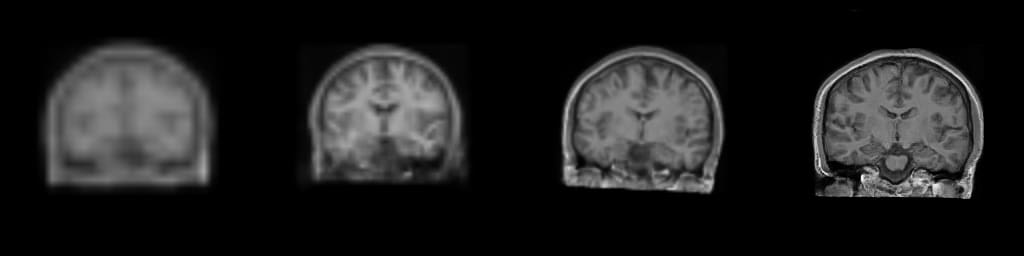

Figure: Progressive generation of T1-weighted brain MR scan starting

from a resolution of 32 to 256 (Left to Right: 323, 643,

1283, 2563). The brain scans are generated using the same

latents in all resolutions. It took about 6 milliseconds for the model to generate

the 2563 brainscan using an NVIDIA TESLA V-100.